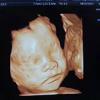

孕期做四维必不可少,各位准妈妈必看 孕期为了宝宝的健康发育, 准妈妈们都会到医院做四维彩超检查。 ...

今天就让我们一起看看关于四维彩超的知识吧。